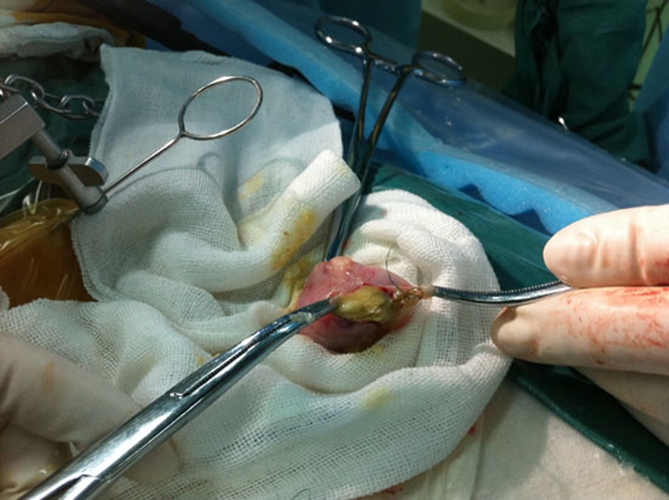

巧克力囊腫圖片

實拍巧克力囊腫